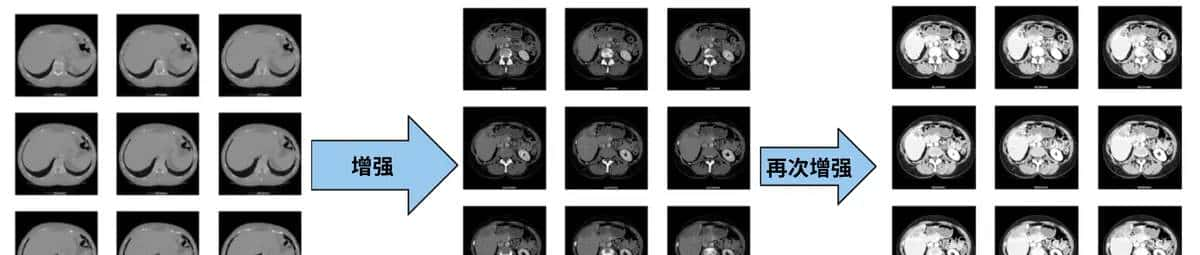

4.图像数据增强

数据增强也叫数据扩增,意思是在不实质性的增加数据的情况下,让有限的数据产生等价于更多数据的价值。

可以上一步整理好的照片和掩模图进行缩放、旋转、裁切、位移等等,用以增加样本量。增强时注意以下几点:

1.生成的新照片色彩模式为黑白灰度,不要用RGB彩色模式

2.CT照片和对应标记了肿瘤的掩模图要做一样的处理且命名上成对匹配

3.根据训练机器的配置,自行调整生成的数量,可多可少,越多当然训练效果越好但训练成本更高